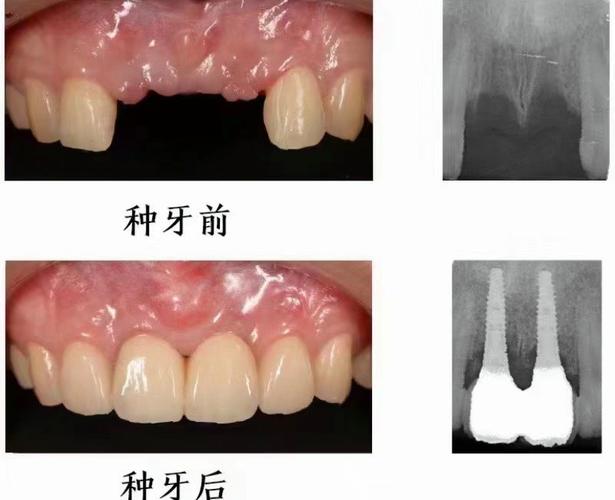

(图片来源网络,侵删)- 影像学检查不充分: 术前CBCT(锥形束CT)拍摄不准确或解读有误,未能精确评估牙槽骨的宽度、高度、密度、形态以及与邻牙、上颌窦、神经管等重要解剖结构的关系,特别是颊侧骨板厚度不足时,未能提前预判。